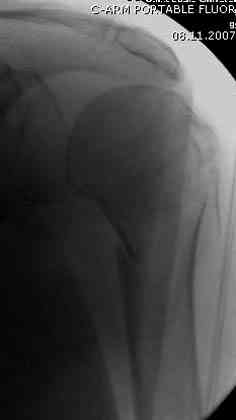

Снимки на 1-е сутки после репозиции и на 8- сутки после репозиции.

Пожалуйста

С ув. Sergey A. Melashenko, г. Запорожье